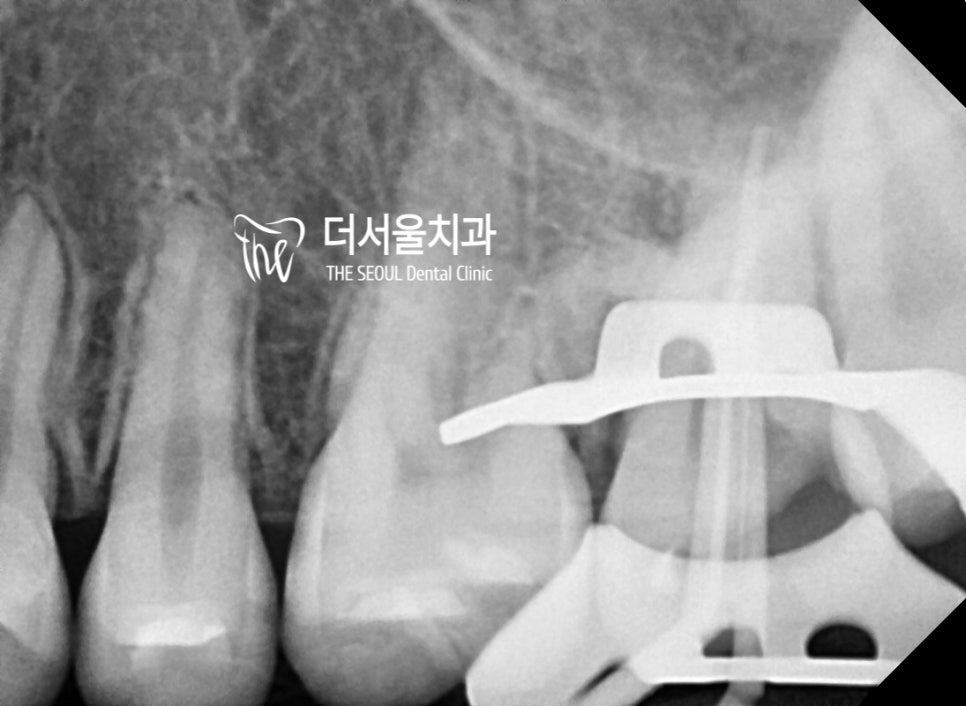

3. 신경치료 진행

신경치료를 할 때 방습환경을

갖추는것이 상당히 중요하며

러버댐과 클램프를 동원하여

진료를 해야 좋은 결과를

얻을 수 있다는 것을요.

그래서, 신경치료를 할 곳에는

사진에서 보실 수 있는 것 처럼

클램프와 러버댐을 낀 채로

근관수복을 진행하게 됩니다.

치아 뿌리 속에 있는

혈관 조직 및 신경 조직들을

깨끗히 제거를 한 다음에

여러 약제를 사용하여

소독과정을 거치게 되죠.

그렇게 방습환경이 갖춰진 상태에서,

근관 내 충전재료의 밀폐가 완성되었습니다.

치아 형태의 축소판처럼 하얀색으로

충전 재료들이 꽉 차 있는 것을 볼 수 있죠.